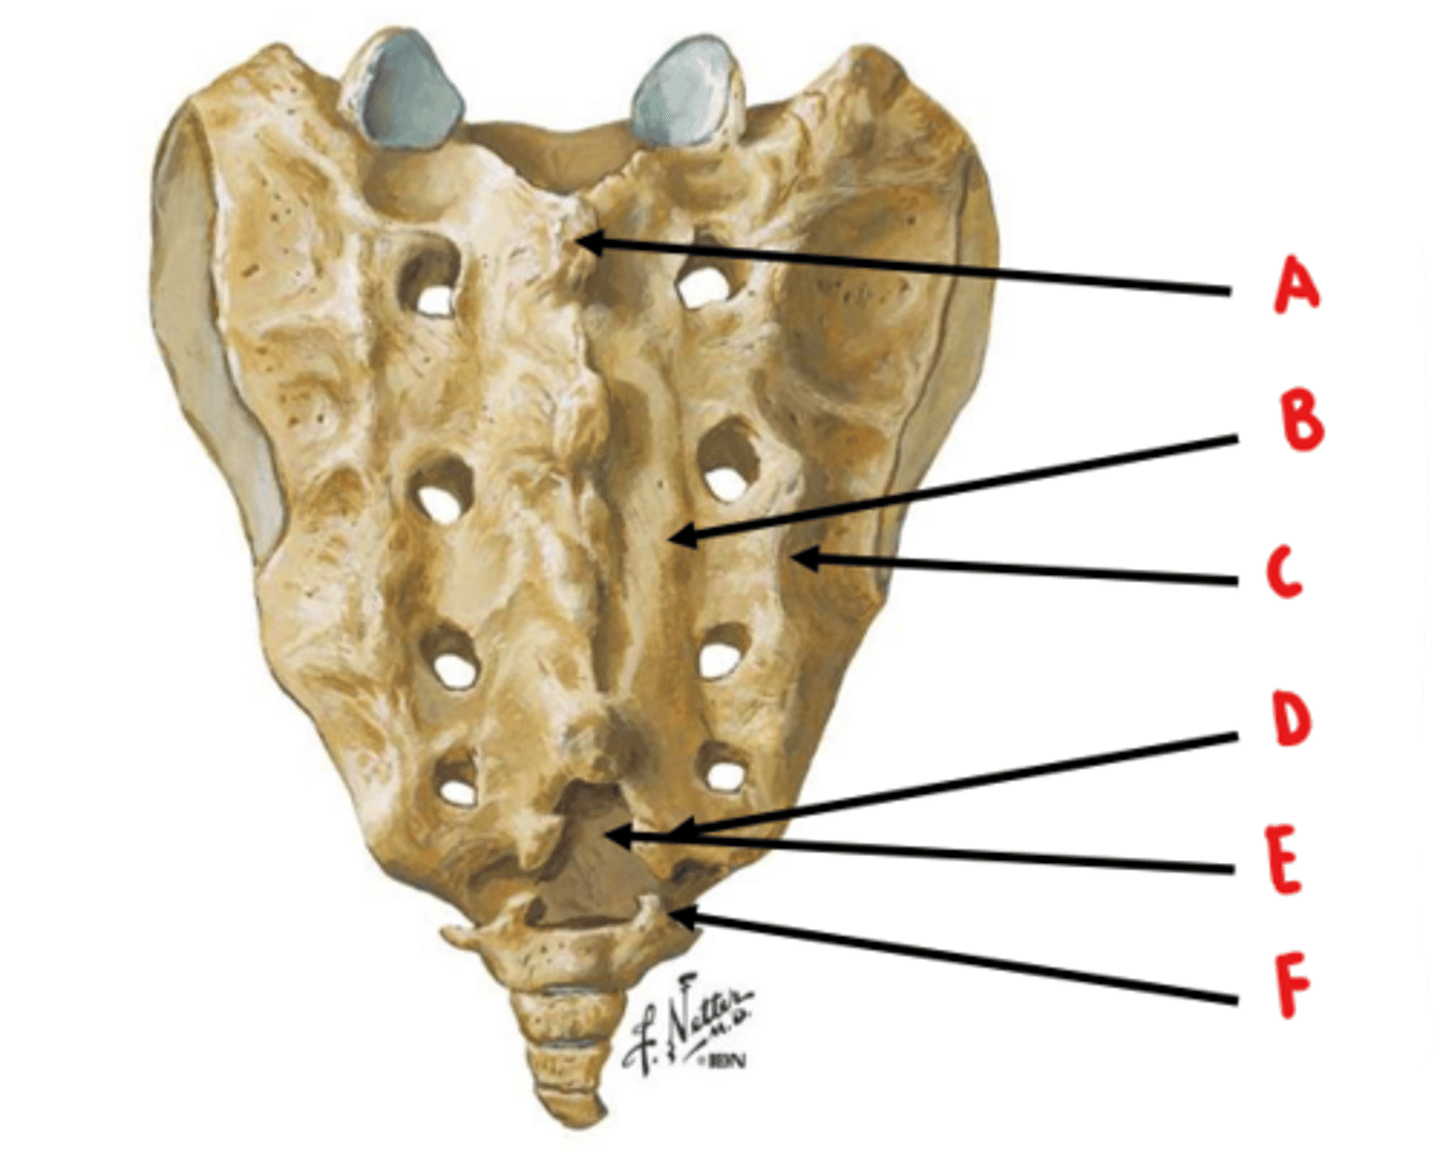

median sacral crest

Identify A

medial sacral crest

Identify B

lateral sacral crest

Identify C

sacral cornua

Identify D

sacral hiatus

Identify E

coccygeal cornua

Identify F

anterior sacral foramen = ventral rami

posterior sacral foramen = dorsal rami

ventral rami are larger because they innervate a larger area of tissue

What structures exit through the anterior and posterior sacral foramen? Which is larger and why?